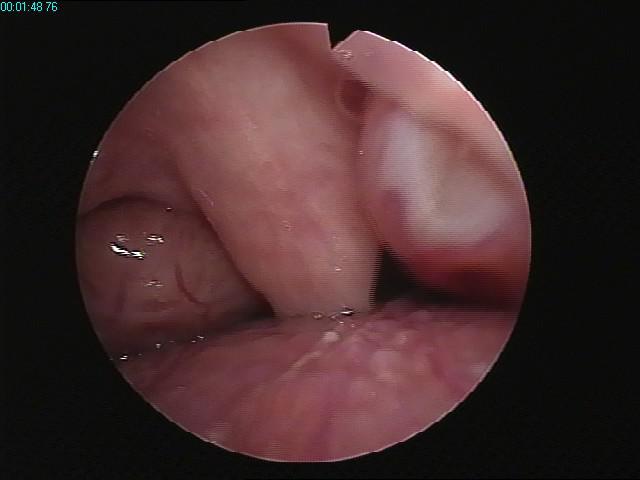

4、扁桃体过度肥大可引起呼吸困难、咽下困难,或言语含糊不清,多见于幼儿患者。

慢性扁桃体炎在某些特定情况下容易形成病灶,引起许多严重疾病。此外,已有慢性炎症的扁桃体也是外界细菌入侵的重要门户,促使发生各种疾病或使原有疾病加重。儿童时期慢性扁桃体炎的反复发作,不但引起并发症的机会甚多,且可影响身体发育。目前的治疗方法包括:

1、非手术治疗:①中医啄治疗法,主要用于扁桃体肥大患者;②扁桃体隐窝的吸引和注洗法;③中药或中成药口服或含漱;④超声雾化吸入;⑤抗生素,主要适用于咽拭子细菌培养阳性者。

2、手术治疗:目前传统方法有挤切法和剥离法两种。也可根据情况采用等离子手术切除。